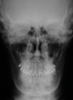

Fig 11. Pretreatment lateral (Fig 11) and posteroanterior (Fig 12) cephalometric x-rays, along with a lateral overjet image (Fig 13). Maxillary deficiency was present in the transverse and sagittal planes.

Figure 11

Fig 12. Pretreatment lateral (Fig 11) and posteroanterior (Fig 12) cephalometric x-rays, along with a lateral overjet image (Fig 13). Maxillary deficiency was present in the transverse and sagittal planes.

Figure 12